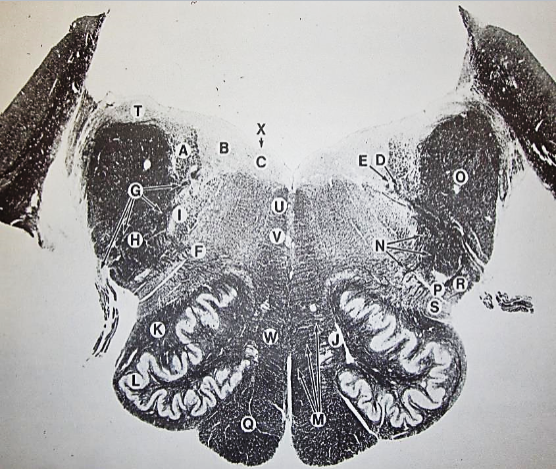

A

fasciculus gracilis

B

gracile nucleus

C

fasciculus cuneatus

D

cuneate nucleus

F

internal arcuate fibers

G

decussation of internal arcuate fibers

H

medial lemniscus

I

hypoglossal nucleus

J

dorsal motor nucleus vagus

K

solitary fasciculus

L

solitary nucleus

M

dorsal longitudinal fasciculus

N

spinal trigeminal tract

O

spinal trigeminal nucleus

P

posterior spinocerebellar tract

Q

anterior spinocerebellar tract

R

spinal lemniscus

S

lateral vestibulospinal tract

T

rubrospinal tract

U

lateral reticular nucleus

V

medial accessary olivary nucleus

W

pyramidal (corticospinal) tract

X

arcuate nucelus

Y

medial longitudinal fasciculus

Z

tectospinal tract

a

fascicles of hypoglossal nerve